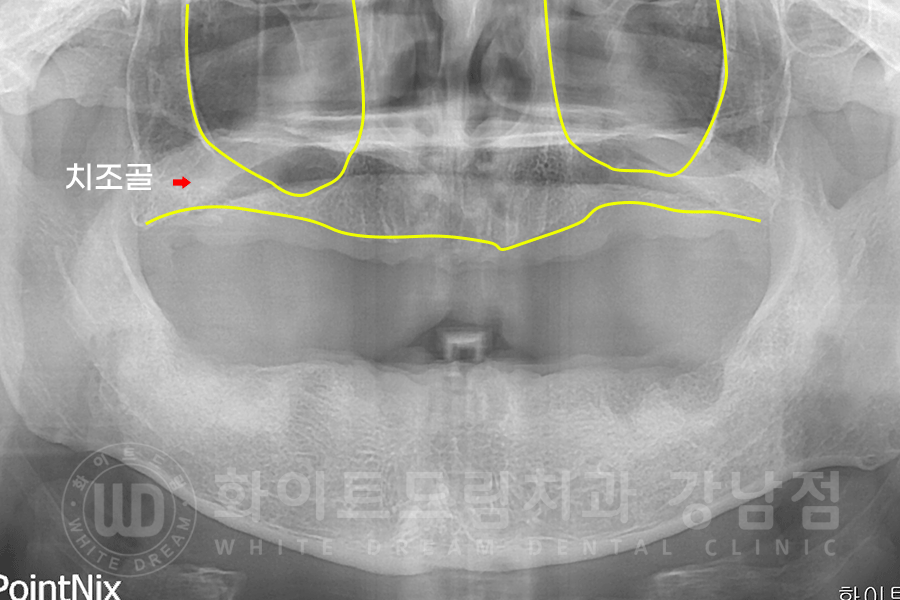

▲ 전악 발치 후 환자분 x-ray 사진입니다. (17.06.03)

1), 2) 상악 치조골은 임플란트를 심기에 뼈의 양이 많이 모자란 상태이기 때문에

뺨 쪽 잇몸에 작은 창을 내어 대량의 뼈이식을 진행하는 lateral 상악동 거상술을 이용하여 진행하기로 했습니다.